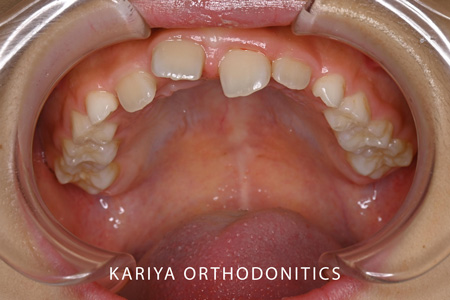

Before

3本の前歯が反対咬合になっている歯並びの1期治療を行いました。

前歯が互い違いになっていると矯正装置がつけずらく、また脱離もしやすいため見た目以上に治療の難易度が上がります。

本症例では、リンガルアーチと補助断線により上顎前歯の唇側傾斜と下顎前歯の舌側傾斜を行いました。